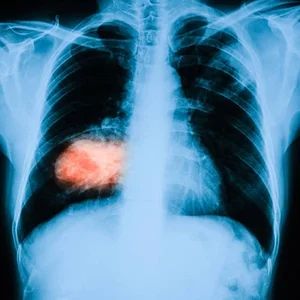

What is Thoracic Cancer?

Thoracic cancer is a type of cancer that develops in the chest area, including the lungs, esophagus (food pipe), and the lining around the lungs. It can affect breathing, swallowing, and overall health if not treated on time. Lung cancer is the most common form of thoracic cancer and requires timely medical attention for better outcomes.

These cancers may develop due to factors like smoking, air pollution, or other health conditions. Common symptoms include a persistent cough, chest pain, shortness of breath, and unexplained weight loss. Early diagnosis and the right treatment approach can help manage thoracic cancer effectively and improve quality of life.

Yes, lung cancer can sometimes be detected early through CT scans or screening in high-risk individuals.